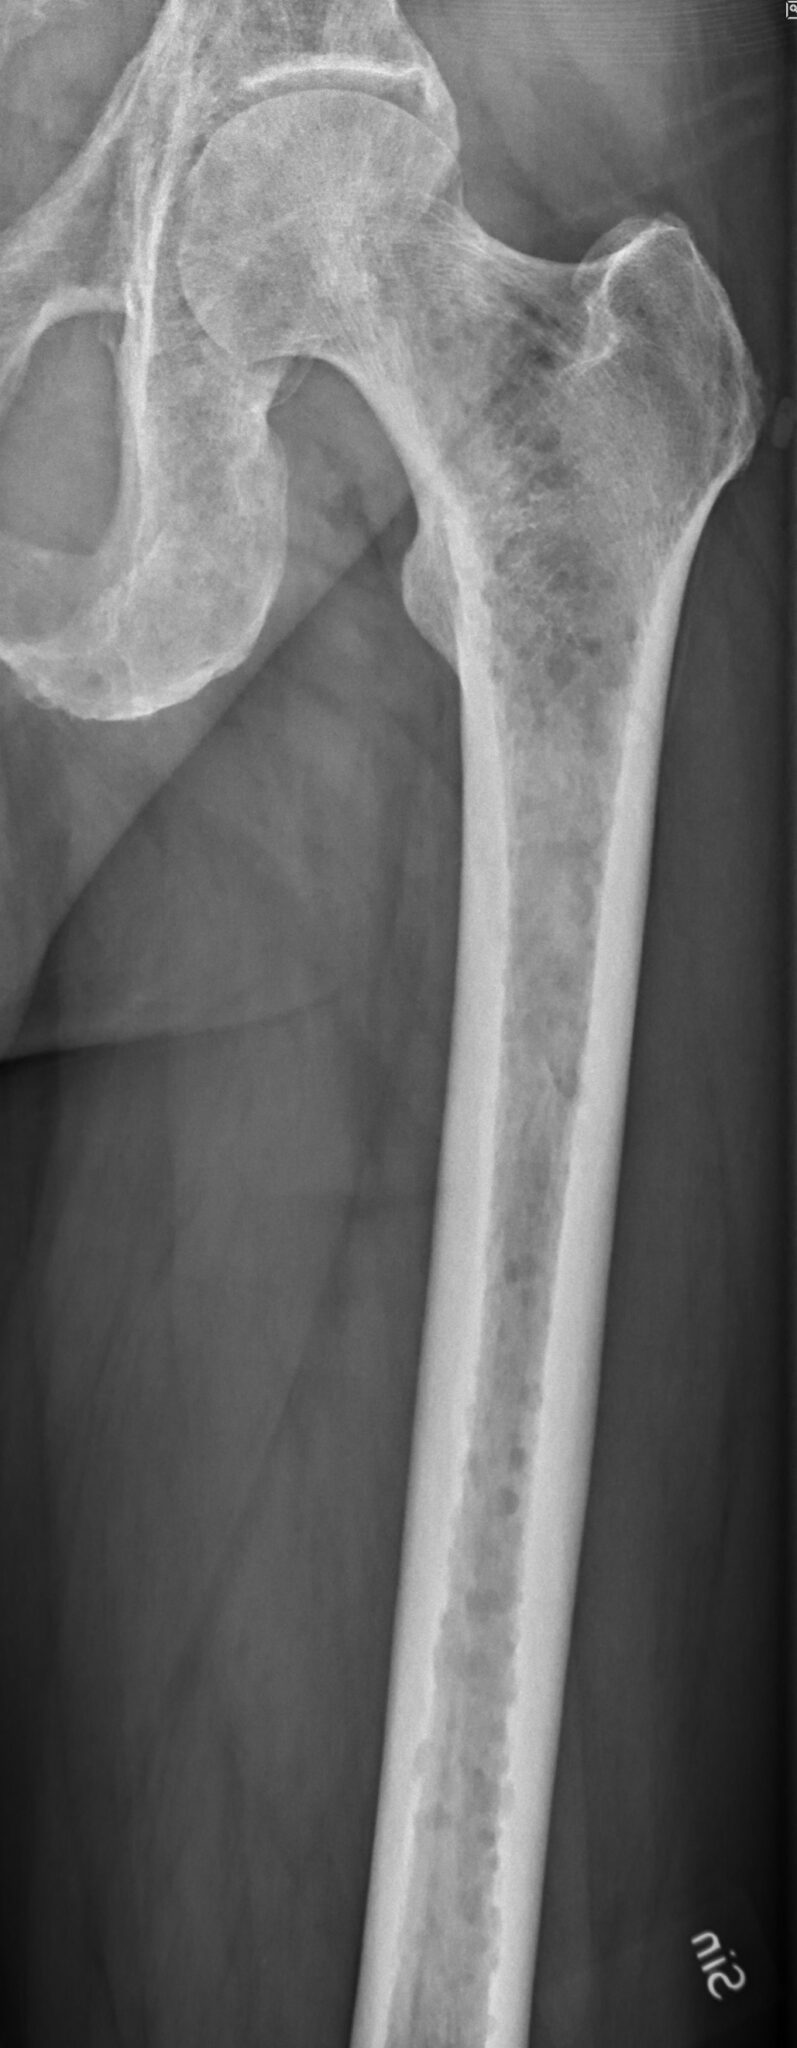

Imaging of Paget Disease of Bone and Its Musculoskeletal Complications Paget's Disease Vs Multiple Myeloma Radiology the role of radiological imaging in multiple myeloma is essentially three. the radiologic features of multiple myeloma could be masked if associated with paget disease. several benign and malignant primary bone tumors involve the calvaria and manifest as lytic, sclerotic, mixed lytic and sclerotic, or thinning. Multiple myeloma and paget's disease of bone show certain. bone. Paget's Disease Vs Multiple Myeloma Radiology.

405. Pagetova choroba Máme rádi internu Paget's Disease Vs Multiple Myeloma Radiology Multiple myeloma and paget's disease of bone show certain similarities such as increased osteoclastic activity and predilection. the radiologic features of multiple myeloma could be masked if associated with paget disease. several benign and malignant primary bone tumors involve the calvaria and manifest as lytic, sclerotic, mixed lytic and sclerotic, or thinning. bone marrow biopsy revealed coexistence. Paget's Disease Vs Multiple Myeloma Radiology.

Paget's disease Stock Image M240/0488 Science Photo Library Paget's Disease Vs Multiple Myeloma Radiology the role of radiological imaging in multiple myeloma is essentially three. several benign and malignant primary bone tumors involve the calvaria and manifest as lytic, sclerotic, mixed lytic and sclerotic, or thinning. bone marrow biopsy revealed coexistence of both mature plasma cells. Multiple myeloma and paget's disease of bone show certain. the radiologic features of multiple. Paget's Disease Vs Multiple Myeloma Radiology.